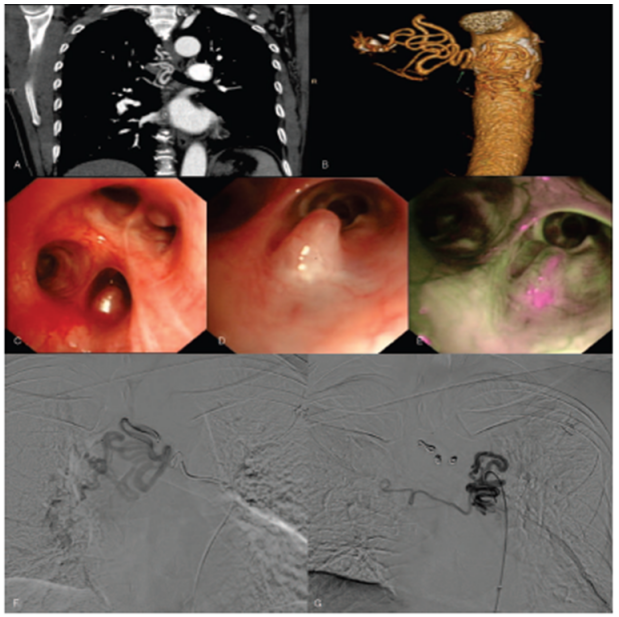

术中在胸主动脉附近寻找支气管动脉,可见左右侧支气管动脉共干,共干血管起始至左侧支气管动脉全程增粗,迂曲,远端可见假性动脉瘤和增生异常血管;右侧支气管动脉正常,未见明显增粗异常。微导管超选择入左侧支气管动脉后,先给予350~560 μm的PVA颗粒栓塞,因血流缓慢,颗粒顺血流栓塞不满意,冲洗导管后予以较稀的液体胶(胶:碘化油=1:4)栓塞,远端血管和动脉瘤铸型,复查造影栓塞满意,未见动脉瘤和异常血管显影。左侧支气管动脉保留,主干保留。

视频:支气管动脉栓塞术

手术当天及术后2天床旁胸片如图4所示。术后第2天更换气管导管,右肺出现实变影。

图片

图4  患者手术当天及术后胸片

CT血管成像(CTA)表现:病变的支气管动脉主干增宽,明显迂曲,管腔没有逐渐变细的趋势,符合“恒径动脉”的表现。气管镜表现:光滑性结节样隆起;充血粗糙,凸起表面覆盖黄白色分泌物形成“小白帽”样表现。支气管动脉造影:病变部位血供丰富,支气管动脉迂曲扩张呈串珠状(图8-图10)

图8  支气管动脉迂曲扩张,呈串珠状

图9  支气管动脉走行于黏膜下,形成结节样隆起

图10  Dieulafoy'病